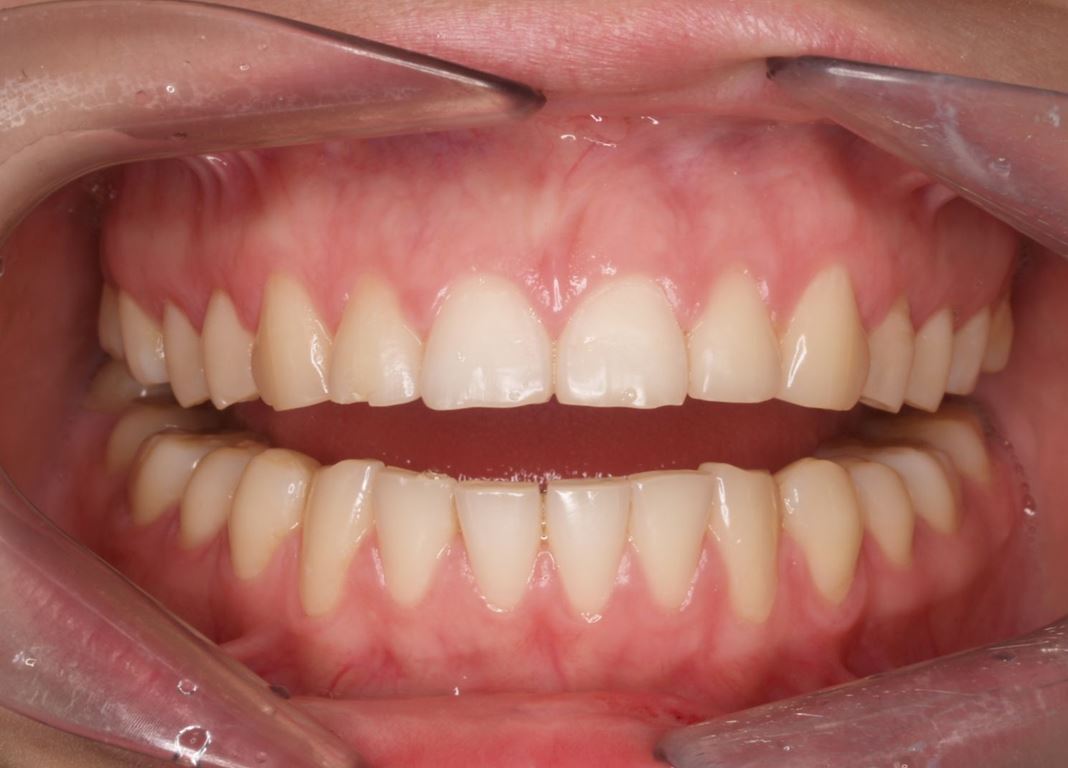

W pierwszym etapie diagnostycznym wykonano zdjęcia zewnątrz- i wewnątrzustne (ryc. 1-12).

Ryciny 39-50 przedstawiają stan po zakończeniu leczenia.